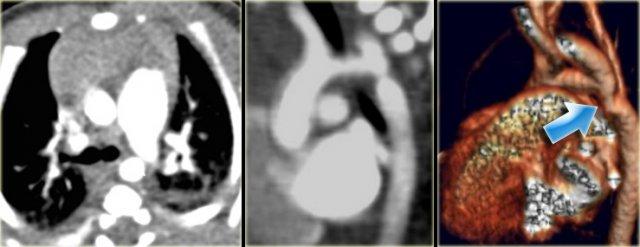

On the far left a patient who was treated with a stent.

The stent ruptured causing restenosis.

Next to it two patients with pseudo-aneurysm.

One after angioplasty and another who developed a pseudo-aneurysm after stent placement.

They have to be repaired because they will rupture.

Pseudo-aneurysms are seen in

- 10% after angioplasty.

- 30% after patch aortoplasty.